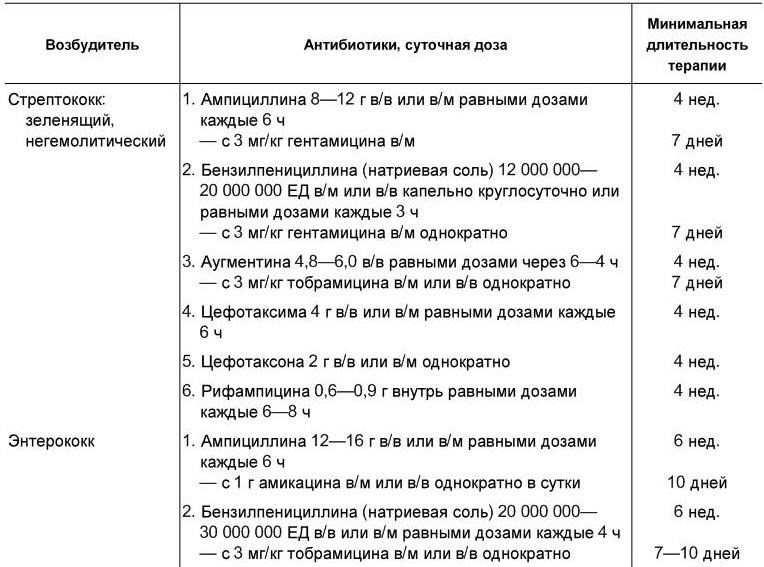

Лечение. Диагноз инфекционного эндокардита или подозрение на его наличие – повод для госпитализации больного. Основа терапии – антибактериальные препараты. Лечение начинают сразу же после взятия крови на посев, а при остром течении – немедленно после постановки диагноза. В первые дни (до получения результатов посева крови) препараты подбираются эмпирически. Обычно исходят из того, что наиболее часто возбудителями являются стрептококки. После получения данных о возбудителе и его чувствительности в терапию вносятся коррективы [Гогин Е. Е., Тюрин В. П., 1997]. Рекомендуется комбинированное введение антибиотиков парентерально в полных терапевтических дозах (табл. 1.13). При грибковых эндокардитах обычно используется амфотерицин В. Он вводится медленно капельно внутривенно в дозе не менее 1,0 г в сутки.

Таблица 1.13

Антибиотики, применяемые при инфекционном эндокардите в зависимости от этиологии болезни

[Гогин Е. Е., Тюрин В. П., 1997]

Длительность терапии определяется исчезновением клинико-лабораторных признаков воспаления, но она не должна быть короче четырех недель даже при самом благоприятном ответе на терапию. Как правило, снижение температурной реакции отмечается через 3 – 7 дней после начала терапии. Длительная антибактериальная терапия может осложняться различными побочными действиями, в том числе ухудшением функционального состояния почек. Нефротоксичность наиболее характерна для гентамицина.